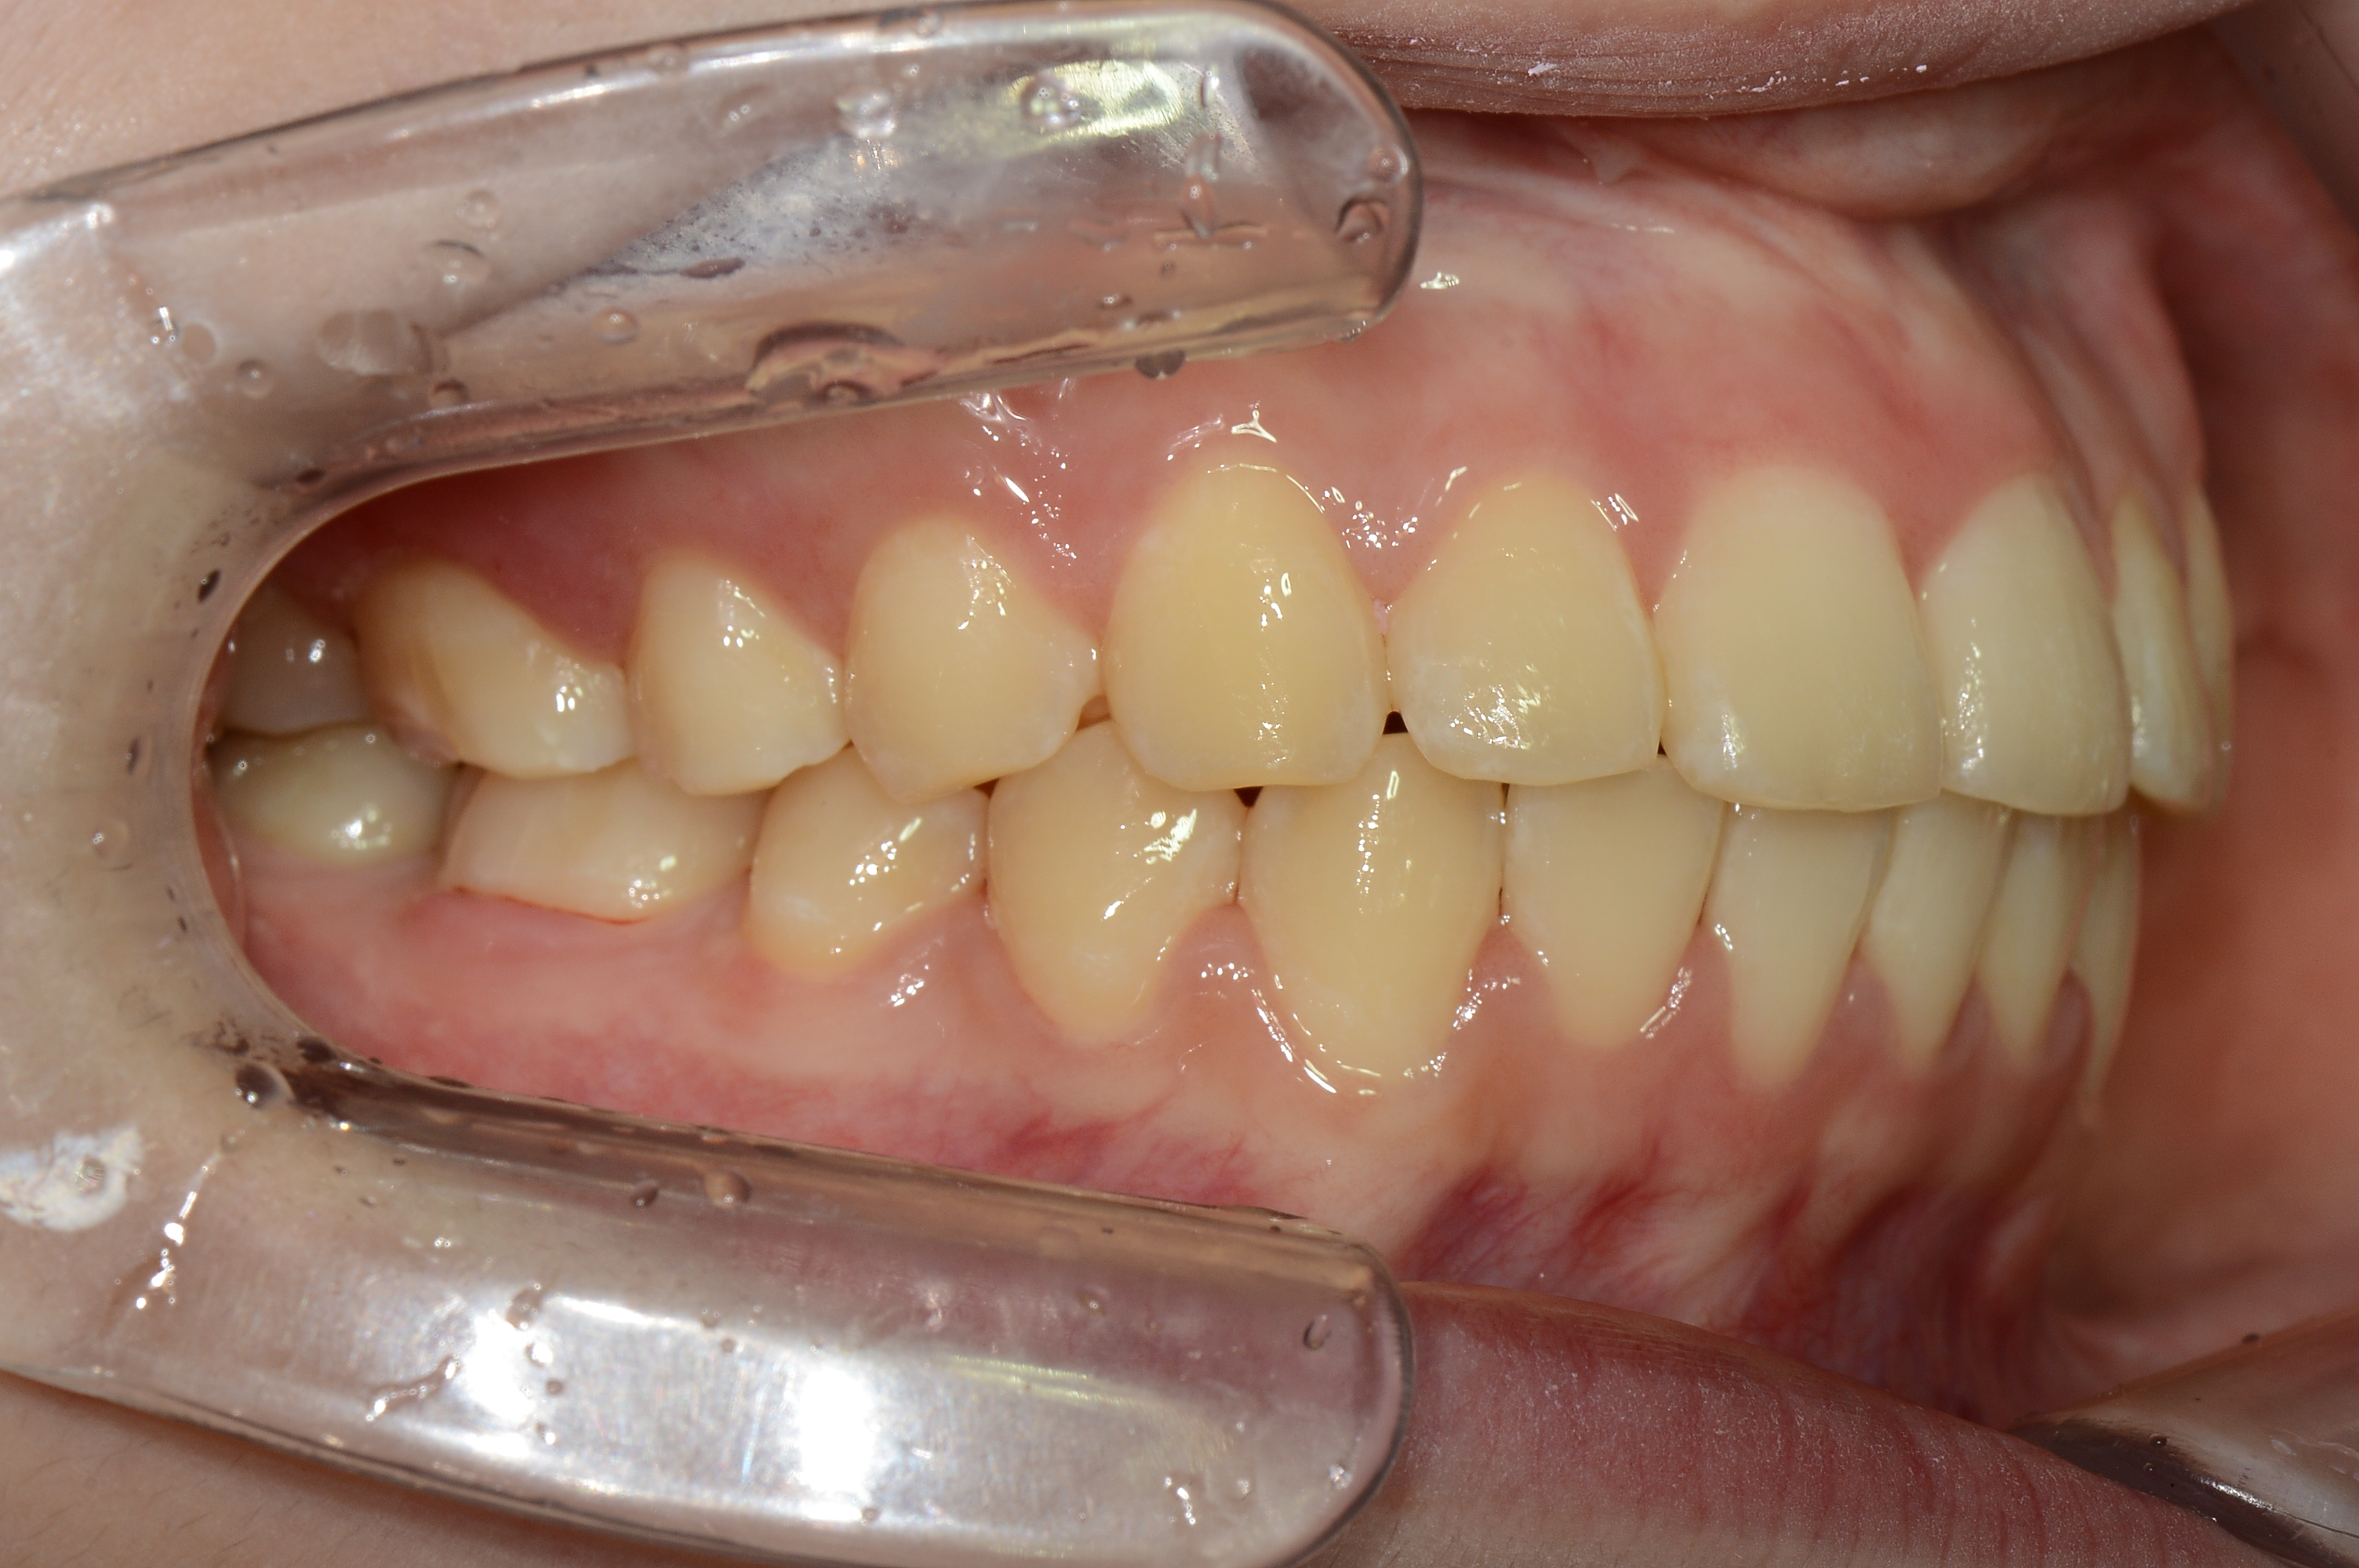

치료 후 사진입니다.